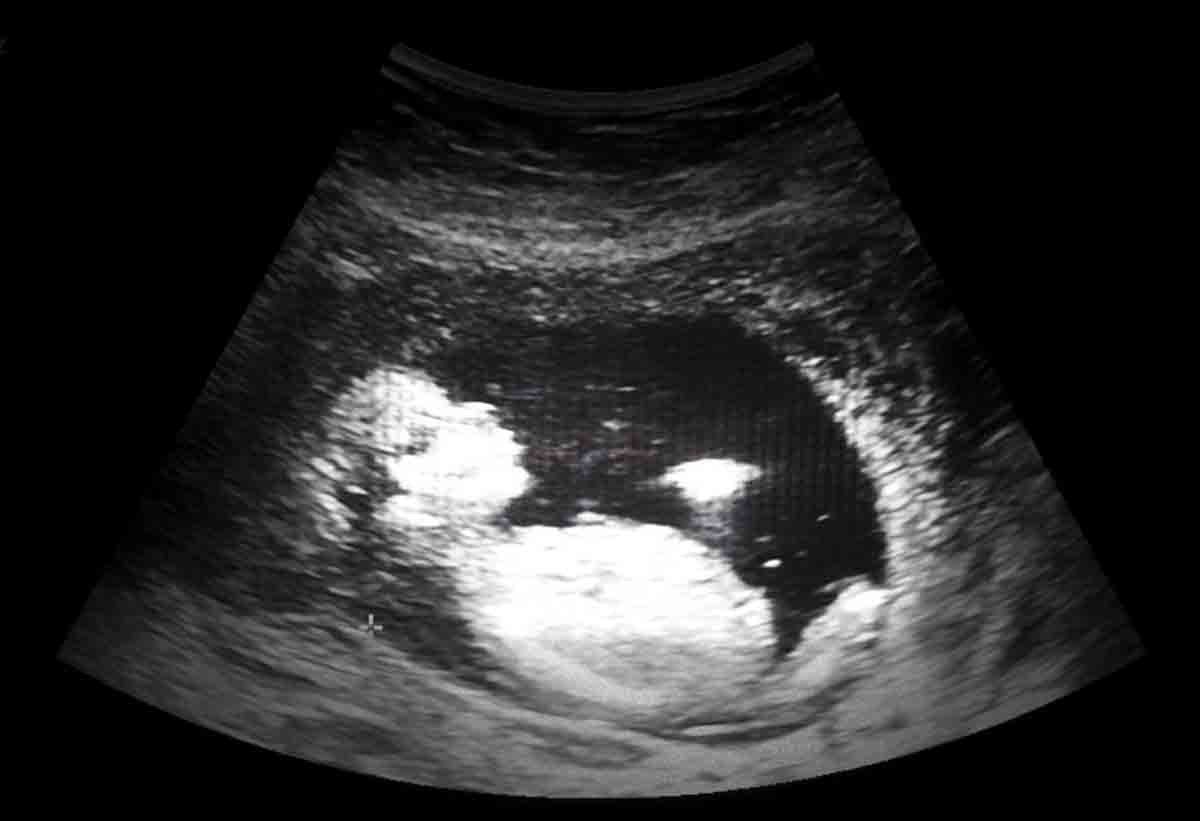

Representational Image

Ultrasound imaging technique is used to capture real-time images inside the human body. It has a wide range of clinical applications in diagnosis and treatment of medical conditions. The technique is widely used to diagnose the cause of pain, swelling and infection in internal organs and to examine foetus in pregnant women.